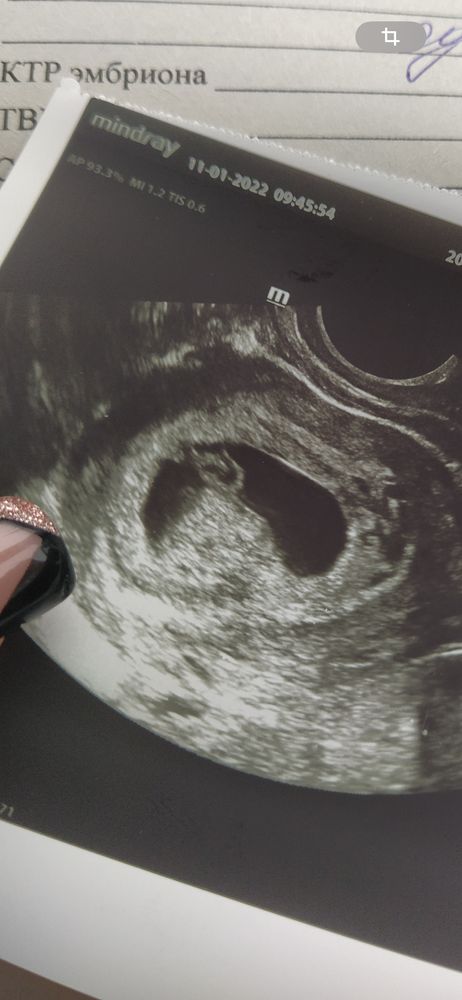

Алена, ага, интересно 😅 вот с сыном так было Изображение

Виолетта, ну вот с сыном понятно) а сейчас на первой фотке если не приближать будто кот сидит 🤣